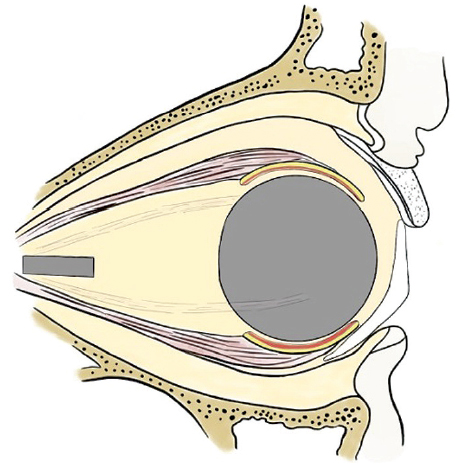

Fig. 5. Condition after enucleation, neurectomy, formation of a supporting-motor stump: implantation of a spherical endoprosthesis, the extraocular muscles are connected to the endoprosthesis

Рис. 5. Состояние после энуклеации, неврэктомия, формирование ОДК: имплантация сферического эндопротеза, глазодвигательные мышцы подшиты к эндопротезу

Fig. 15. Installation of an external cosmetic prosthesis congruent with the supporting-motor stump after removal of the eyeball by enucleation

Рис. 15. Положение наружного косметического протеза, конгруэнтного с ОДК после удаления глазного яблока методом энуклеации